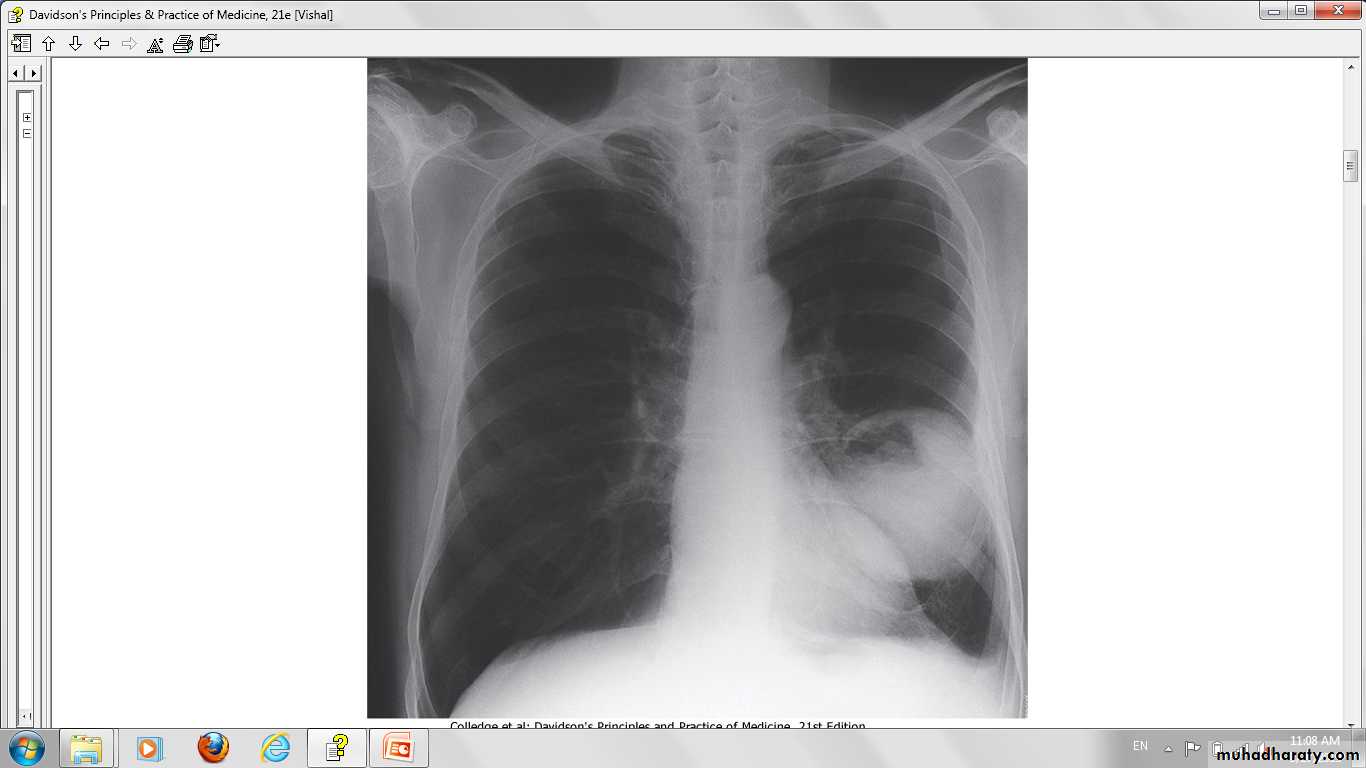

Lung cancer in right lung Chest X-ray.